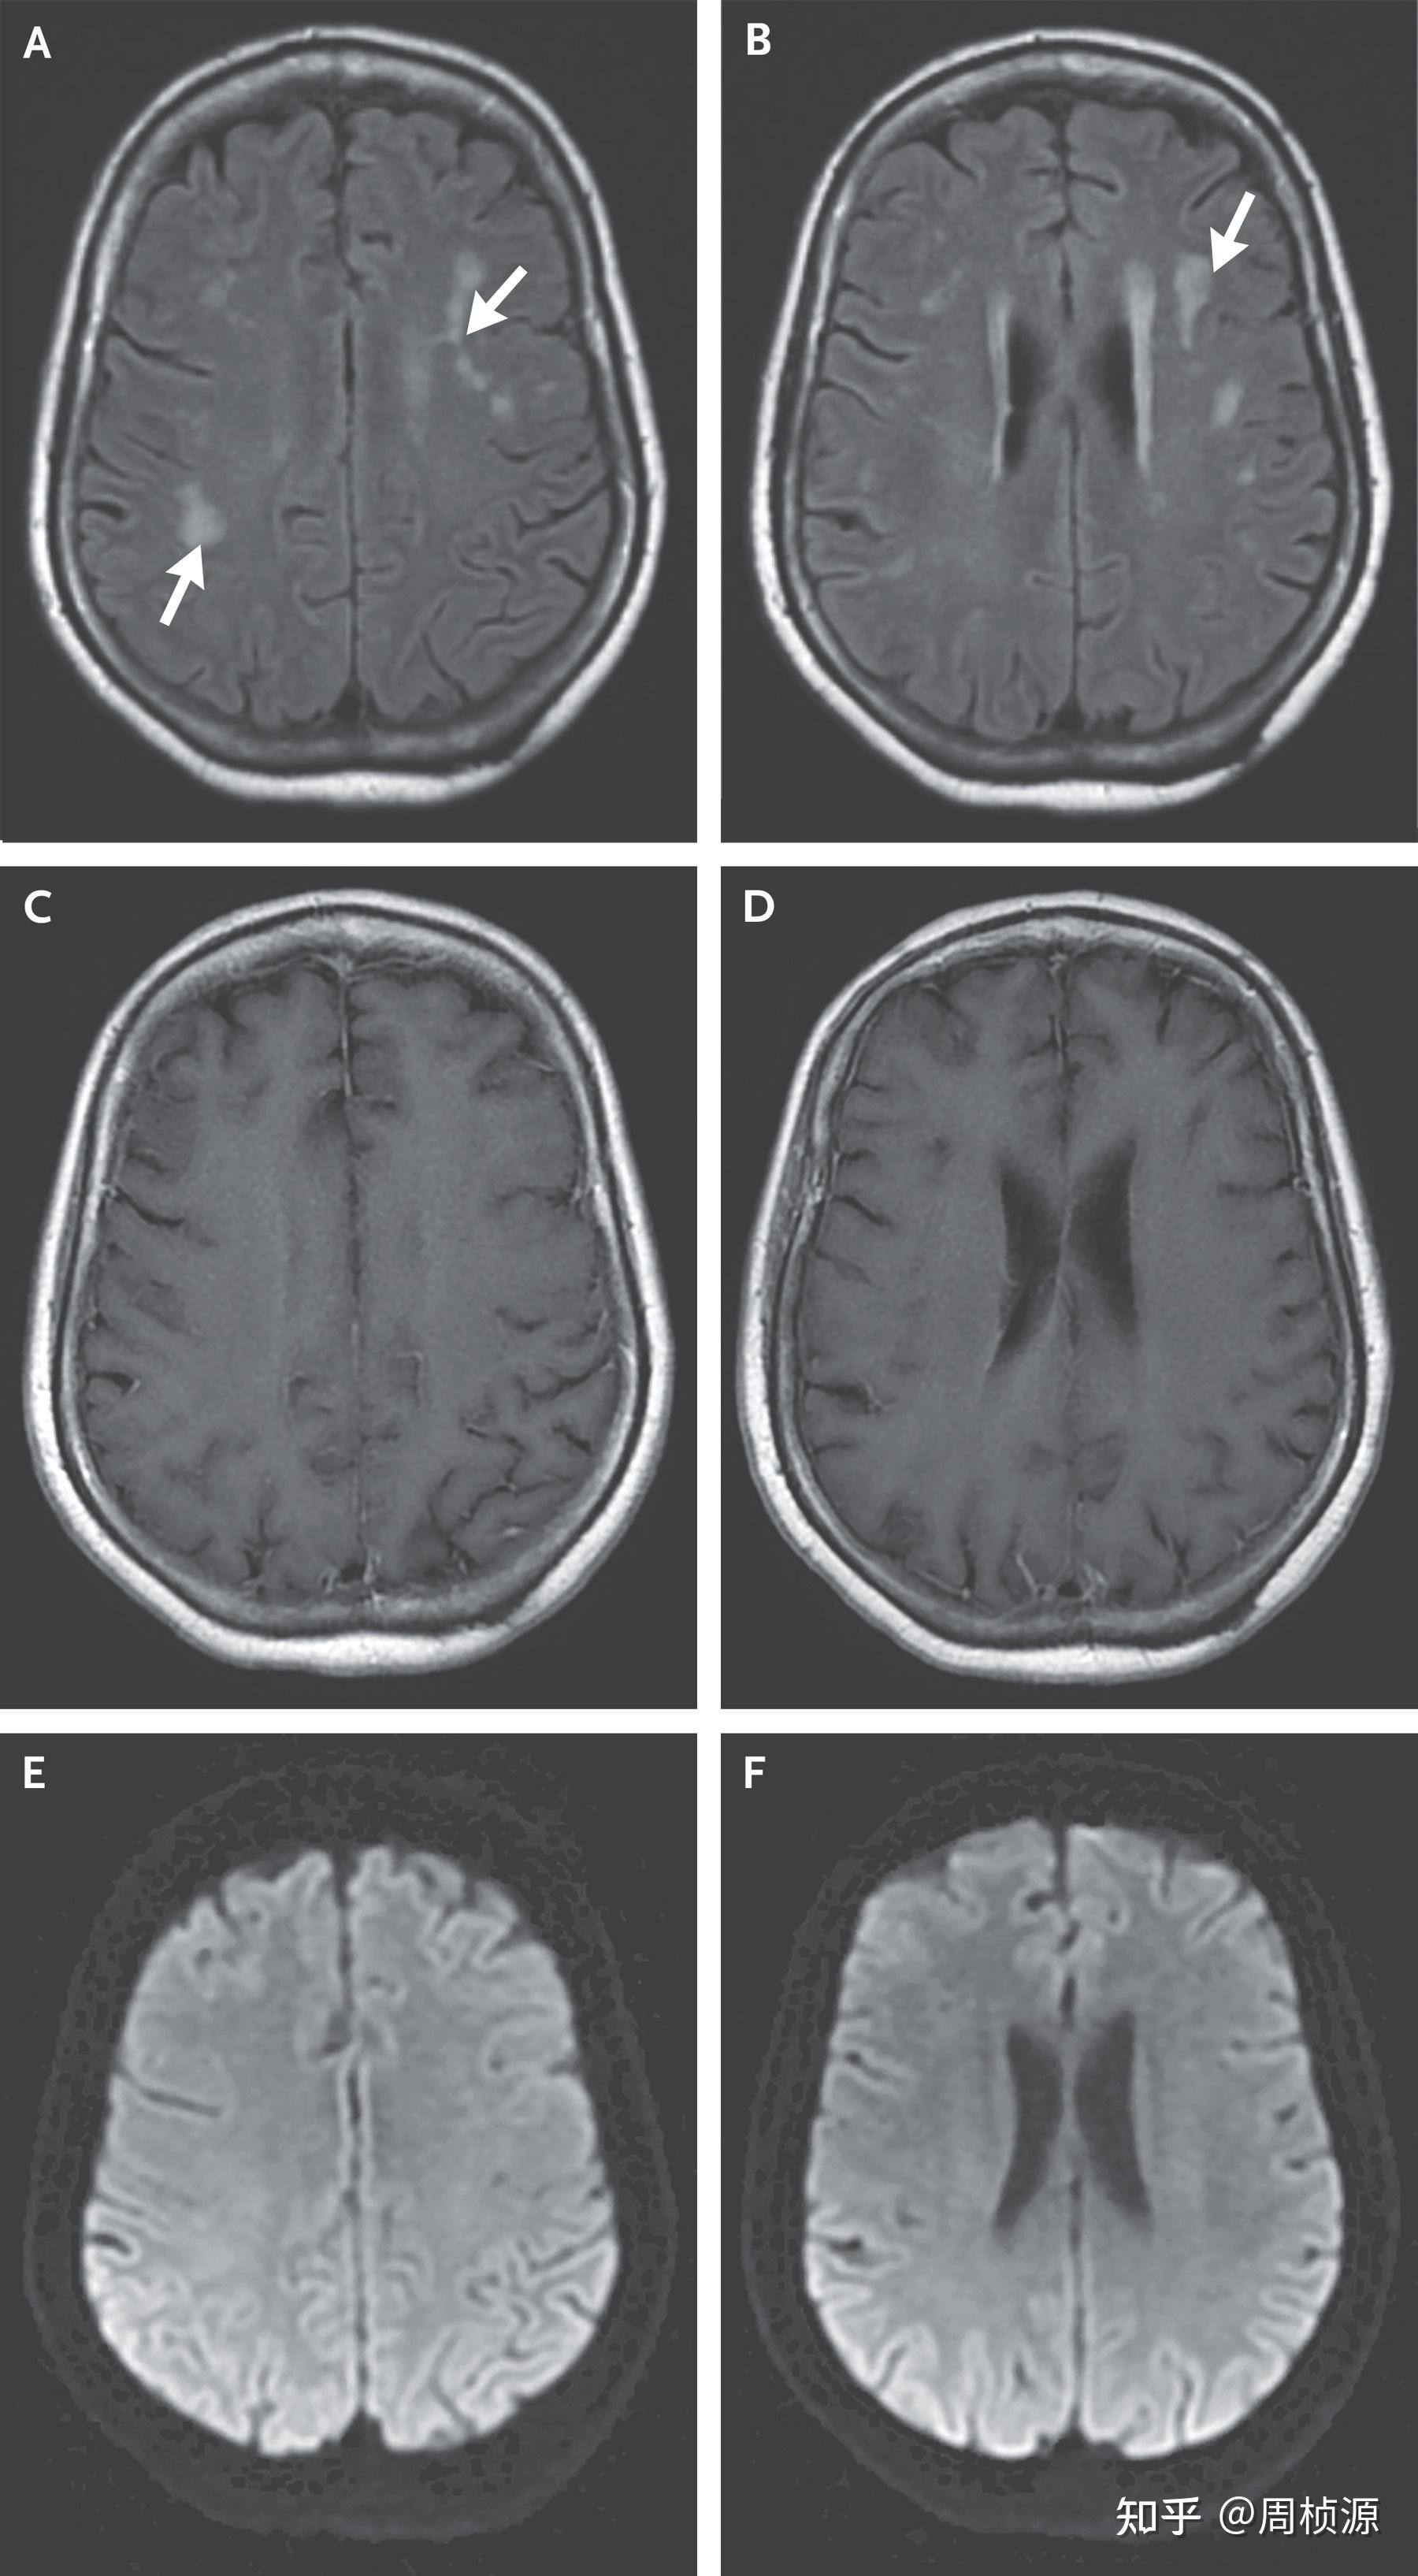

Nejm 2021 Case 22 知乎 Nejm Case Report 2021 presentation of case. presentation of case. Authors pavan k bendapudi 1 , michael j whalen 1 ,. presentation of case. sep 26, 2024. presentation of case. Nejm Case Report 2021.